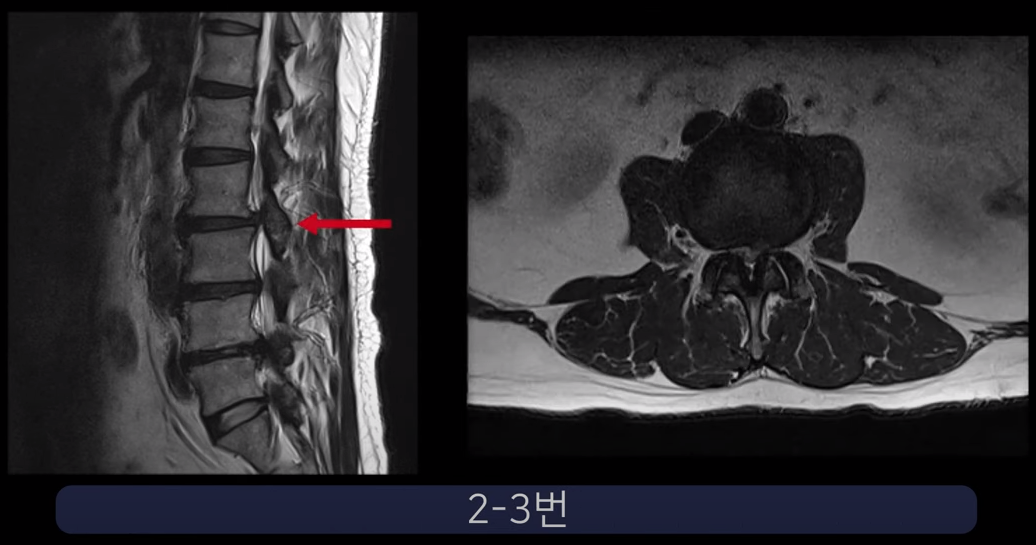

실제 척추관과 추간공이 심하게 막힌 두 환자 케이스를 보여드리겠습니다.

첫 번째 환자분입니다. 이 환자분은 허리 세 마디에 심한 협착이 있습니다. 2-3번, 3-4번, 4-5번 이렇게 척추관이 세 마디가 심하게 막혀있습니다.